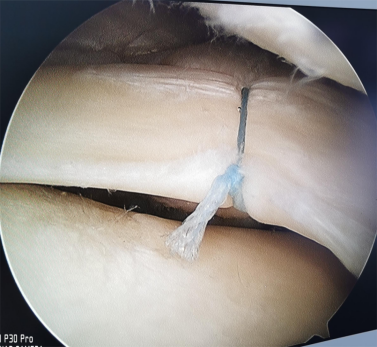

半月板损伤修补术

1.急性膝关节损伤:如,创伤性血肿、交叉韧带损伤、半月板周缘损伤、骨软骨骨折、胫骨平台骨折。